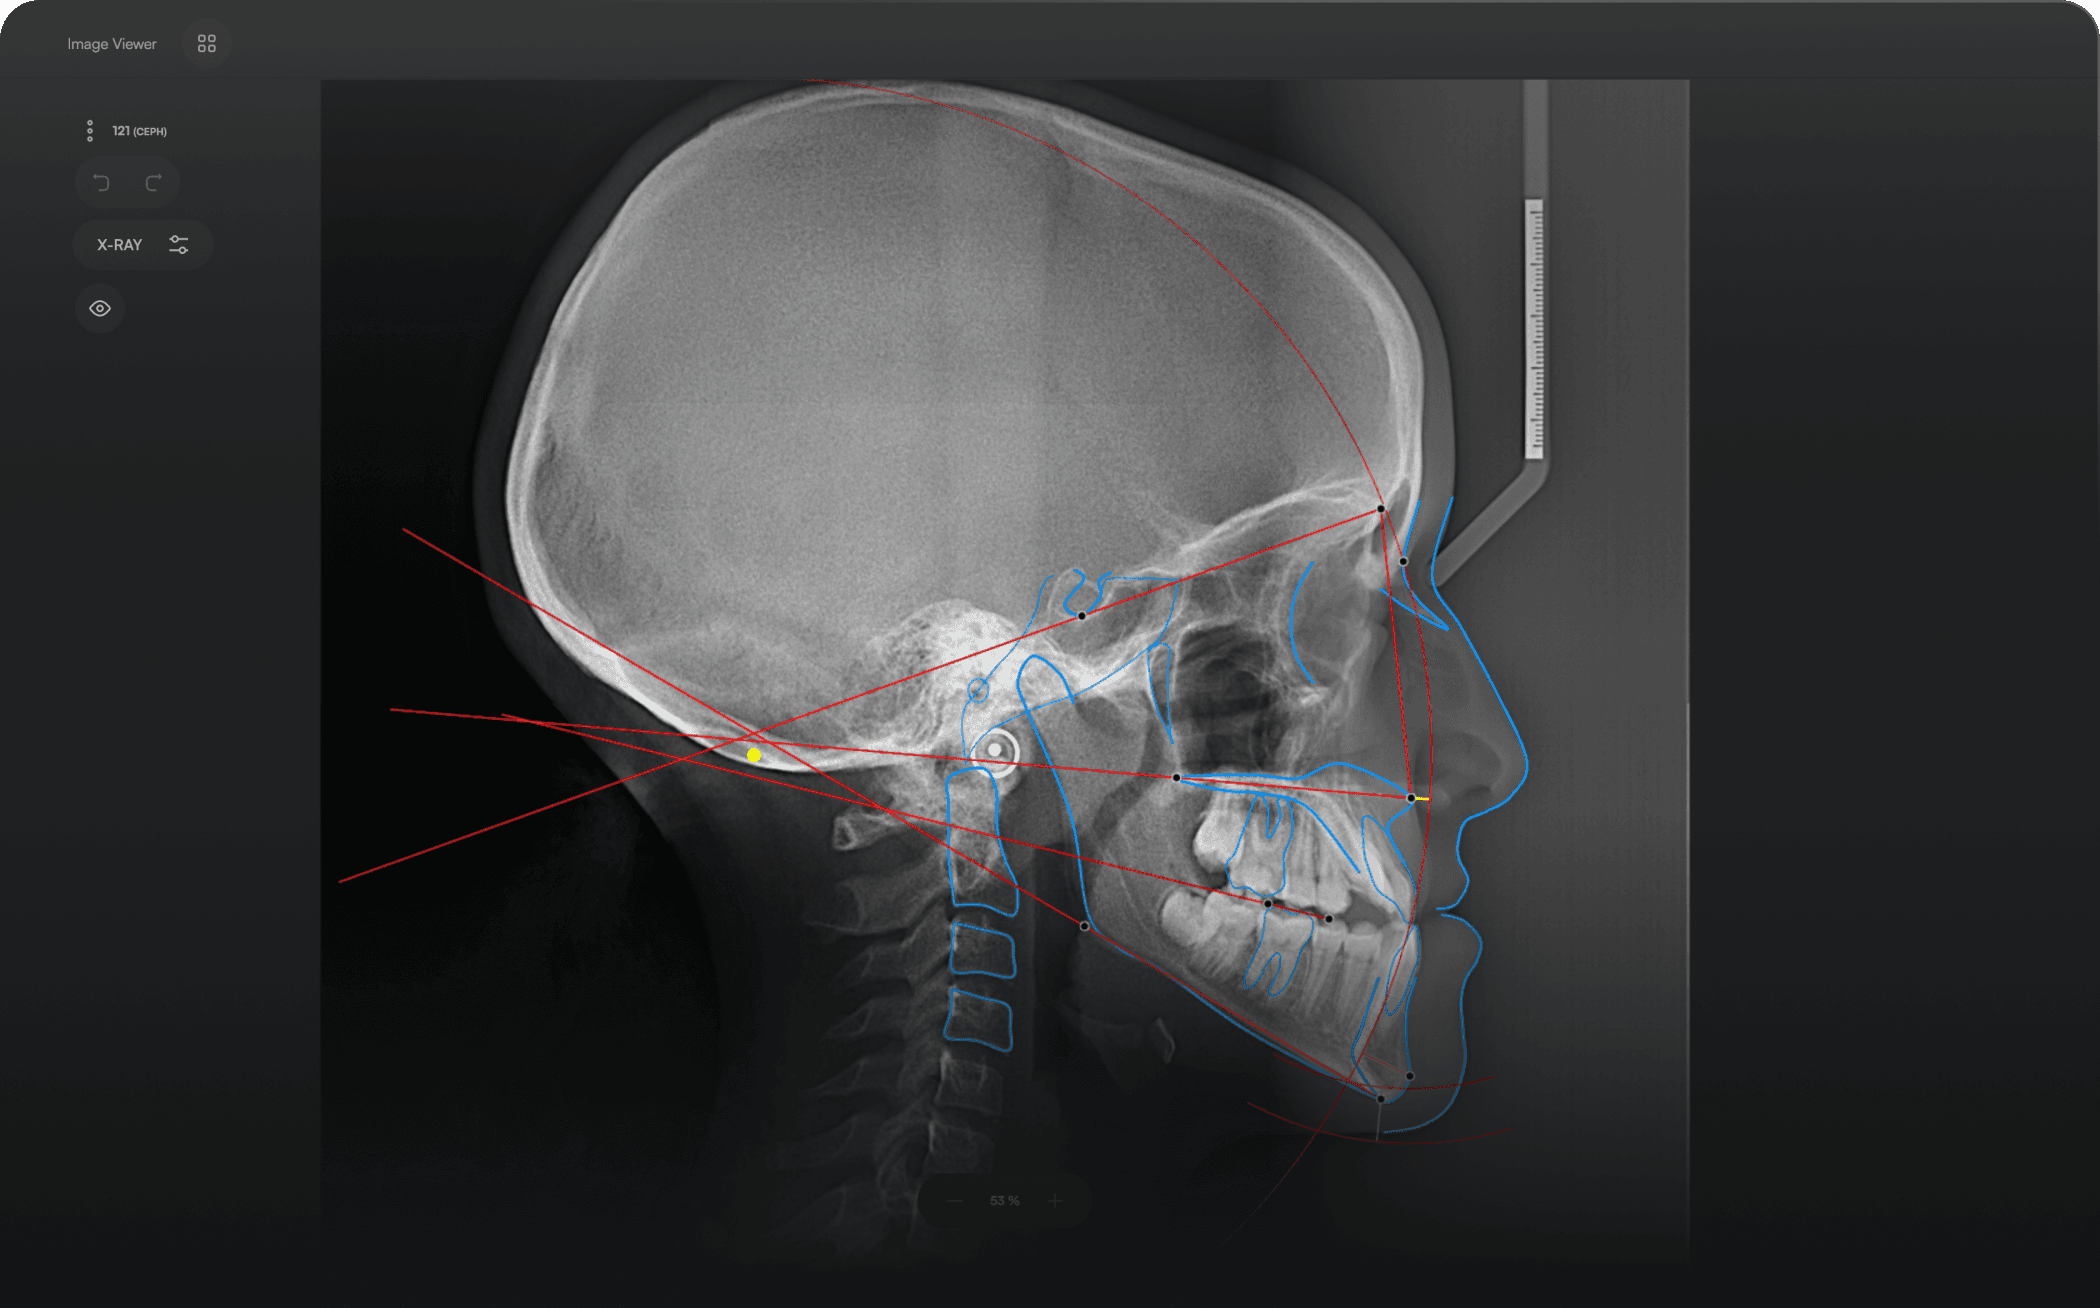

Diverse Analysis

Access automated studies like Steiner and Jefferson to assist in clinical assessment and enhance case evaluations.

Powerful Insights

Experience a comprehensive assessment of skeletal, dental, and soft tissue discrepancies.